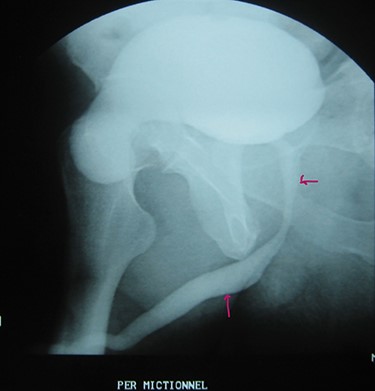

A 72-year-old man with a history of controlled diabetes and hypertension presented to our department with right inguinal swelling and intermittent lower urinary tract symptoms (LUTS) with pollakiuria, dysuria, prolonged micturition time and a sensation of a full bladder after micturition. He reported nausea, vomiting and right lower quadrant paint. The patient also reported having to manually compress the scrotum in order to empty the bladder. Physical examination revealed a slightly painful on palpation and reducible 6 cm right inguinal hernia extending into the right hemiscrotum. The body mass index of the patient was 31.4 kg/m2. His PSA was 4.3 ng/ml. On uroflowmetry, maximum flow rate (Qmax) was 13 ml/s and the voided volume was 180 cc. The uroflow curve was flat. The Bacteriological examination of urine was negative. Retrograde urethrocystography revealed right inguinal hernia containing a portion of the urinary bladder (Figs 1,2). He also had an intravenous urography in order to study the upper urinary tract and to have an idea of the renal function. This radiological exploration confirms the data of the retrograde urethrocystography and illustrates well the bladder hernia. However, a moderate left hydronephrosis with a nonobstructive pyelic calculus of 1.5 cm was observed on intravenous urography (Figs 3,4). Intraoperative findings revealed a direct right inguinal hernia with complete herniation of bladder into the scrotum. The bladder appeared healthy with no signs of injury and was restored to its normal anatomical position without resection. The hernia was repaired with a biologic mesh by the Lichtenstein technique. The patient had an uneventful postoperative course. Concerning his pyelic calculus problem, shock wave lithotripsy sessions were scheduled.

Retrograde urethrocystography: right inguinal hernia containing a portion of the urinary bladder.

Urethrocystography: no obstruction under the bladder in the per mictional image.